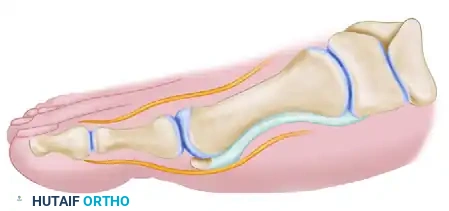

Phase 3: The Proximal Crescentic Osteotomy

The third incision is placed dorsally over the proximal metatarsal to execute the basilar osteotomy.

- Incision and Exposure: Make a dorsal longitudinal incision over the proximal third of the first metatarsal, extending proximally over the medial cuneiform. Retract or ligate the dorsal venous arch and protect the superficial peroneal nerve branches.

- Periosteal Incision: Identify the metatarsocuneiform (MTC) joint. Incise the periosteum longitudinally, medial to the extensor hallucis longus tendon.

- Marking the Bone: Score the dorsal metatarsal transversely at two levels: 1 cm distal to the MTC joint (the osteotomy site) and 2 cm distal to the MTC joint (the screw fixation site).

- Pre-drilling the Glide Hole: Crucial Step. Drill a 3.5-mm glide hole at the 2-cm mark (1 cm distal to the planned osteotomy) in the center of the metatarsal shaft, directing it proximally. Performing this before the osteotomy ensures absolute stability during drilling.

- Executing the Osteotomy: Use a specialized curved crescentic saw blade. The convexity of the blade must face distally.

- Biomechanics: A distally convex cut prevents overcorrection of the intermetatarsal angle and minimizes shortening of the first ray.